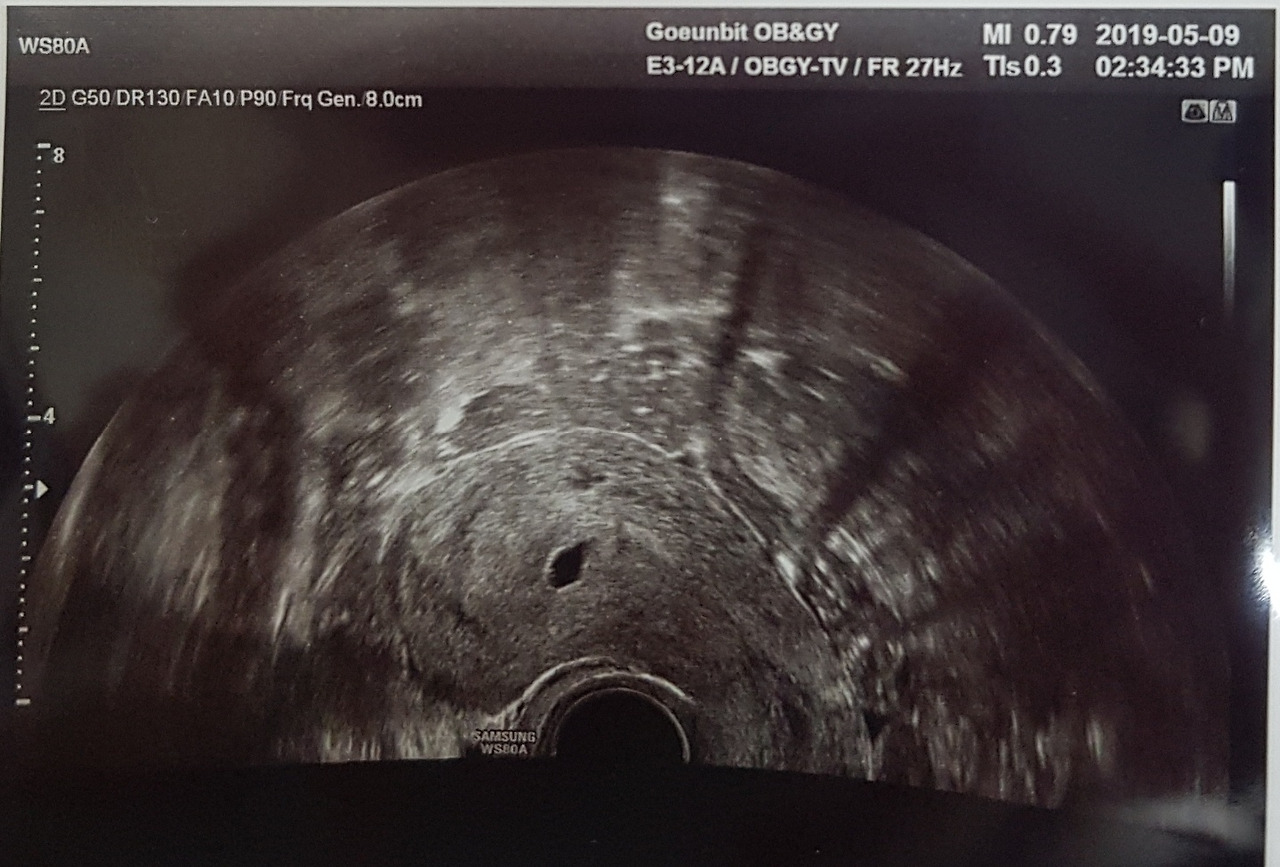

임신 약 4주차. 나의 배 속에는 작은 아기 집이 생겼고, 세포로 시작한 작은 생명은 신기하리만치 건강하게 쑥쑥 잘 자랐다.

하루하루가 전전긍긍이었던 시험관 시기와는 달리 자연적으로 임신을 하니 걱정이 무색할 만큼 쑥쑥 자랐다. 우리의 새 생명은 엄마에게 입덧도, 부종도, 급속한 살찌움도 주지 않고 아주 건강하게 잘 자랐다.